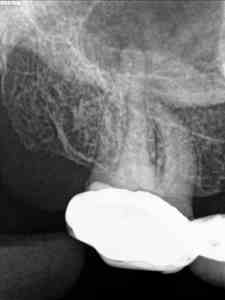

C) Por último, no encontramos un 1.6 con otra pulpitis irreversible.

C)